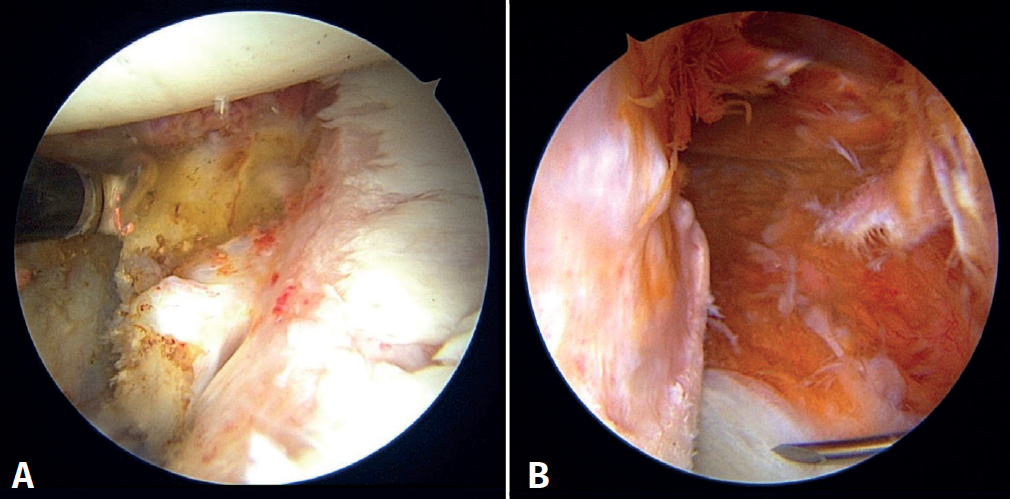

Fourth step: capsulolabral plication and knotting of the remplissage

Once the bone block is secured, the sutures of the implants previously placed at the anterior margin of the glenoid lesion are retrieved, and repair is carried out of the labrum and capsule over the bone graft according to the usual technique. Finally, the suture extremities of the implants placed in the Hill-Sachs lesion are knotted from the posterior portal, reducing the defect and completing the remplissage technique(17). The result obtained is assessed (Figure 7) and the procedure is completed by suturing the portals and immobilising the limb with a standard thoracic bandage.